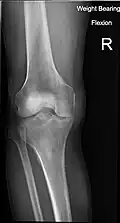

X-ray

-

Knee X-ray -

Knee X-ray (weight bearing) -

Knee X-ray (weight bearing, flexion)